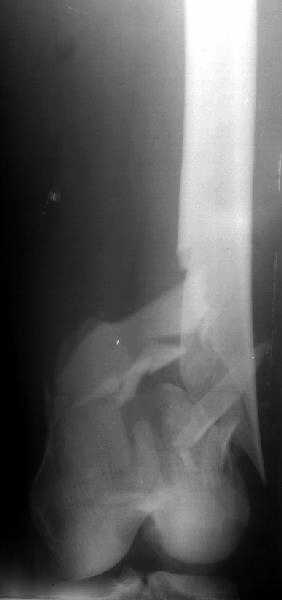

Отправитель: Alexander Chelnokov 28 Декабрь 2003, 21:01

1

2

de> you think you are using antigrade nails for some very low

de> fractures including some intercondylar fractures.

Exactly. It seems the option looks underestimated.

No, i haven't seen such comparisons. However some advantages of closed antegrade nailing vs conventional plating looks self-evident like no site opeining, no bone skeletization, less blood loss, no need for autografting... If you or other colleagues can help me with the references it would be greatly appreciated. I would be interested also to compare ante- vs retrograde nailing for the localization.

I attached an example of C2 fracture with result of the same technique in 5 months.